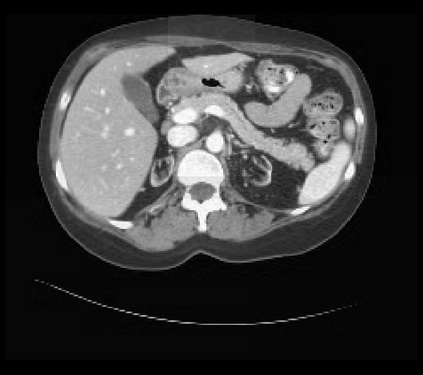

It is imperative to ensure the robustness of deep learning models in critical applications such as, healthcare. While recent advances in deep learning have improved the performance of volumetric medical image segmentation models, these models cannot be deployed for real-world applications immediately due to their vulnerability to adversarial attacks. We present a 3D frequency domain adversarial attack for volumetric medical image segmentation models and demonstrate its advantages over conventional input or voxel domain attacks. Using our proposed attack, we introduce a novel frequency domain adversarial training approach for optimizing a robust model against voxel and frequency domain attacks. Moreover, we propose frequency consistency loss to regulate our frequency domain adversarial training that achieves a better tradeoff between model's performance on clean and adversarial samples. Code is publicly available at https://github.com/asif-hanif/vafa.